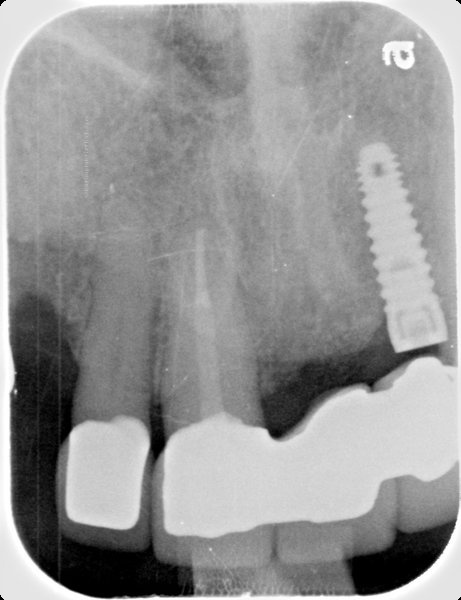

Micro-Vent 2

Connection Interface

Internal interface

Body Shape

Tapered body

Thread Design

ThreadedRounded threads

Straight flangeCurved apexRound hole